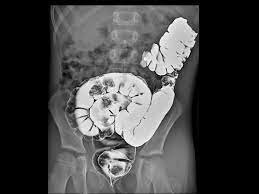

1972 Godfrey Newbold Hounsfield y Allan Mcleod Cormack presentan el primer modelo de tomógrafo computarizado que muestra cortes sagitales, logrando visualizar con más detalle partes internas del cuerpo en especial los tejidos blandos.

1979 Godfrey Newbold Hounsfield y Allan Mcleod Cormack reciben el premio novel por el descubrimiento de la tomografía computarizada.